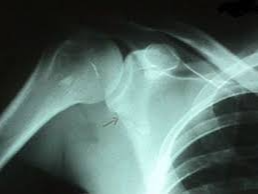

어깨뼈 골절은 어깨 주변을 구성하는 여러 뼈 중 하나가 부러지는 상태를 의미합니다. 어깨는 단순한 관절이 아니라 여러 뼈와 인대, 근육이 복합적으로 연결된 구조이기 때문에 골절의 종류도 다양하게 나타납니다. 흔히 발생하는 골절 위치는 견갑골, 쇄골, 상완골 근위부입니다. 특히 낙상 사고나 교통사고에서는 상완골 근위부 골절이 자주 발생합니다.

이 중에서도 상완골 근위부 골절은 고령자 낙상 사고에서 매우 흔하게 나타나는 골절이며, 경우에 따라 금속 핀이나 금속 플레이트를 이용한 고정 수술이 필요할 수 있습니다.